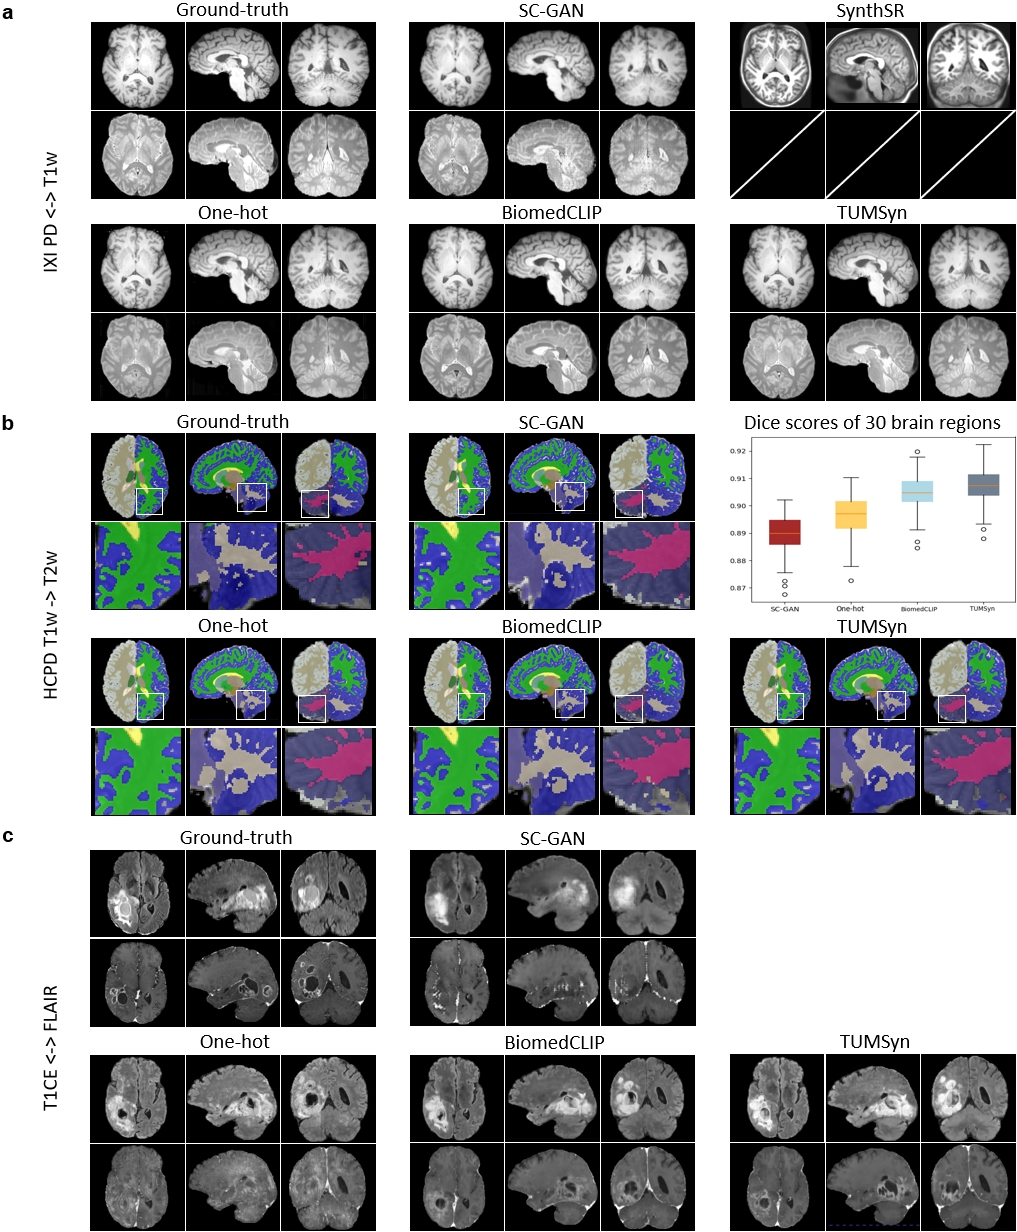

Visual evaluation is presented in Fig. 4. Besides the aforementioned comparison methods, a general method dedicated to synthesizing T1w images, SynthSR [28], is further enrolled into comparison. We observe that, since the PD images in the IXI dataset are acquired from two centers using different imaging protocols, the output images of TUMSyn are much more accurate in anatomical details especially compared to SC-GAN, One-hot model, and SynthSR (Fig. 4 a). These observations once again underscores the importance of utilizing imaging parameters and demographic information as textual prompts to guide accurate image synthesis.

Besides, we further perform whole-brain region parcellation on the HCP development (HCPD) dataset to assess the anatomical structure consistency between synthetic and real-acquired images (Fig. 4 b). Totally 30 brain regions are segmented using Synthseg+ [29]. We compare the parcellation results by our TUMSyn with those by other methods using visual inspection and Dice score. Both qualitative and quantitative evaluations reveal that the generated images by our TUMSyn enable the most precise parcellation.

In addition, we also evaluate the effectiveness of TUMSyn in handling patients with abnormal brain anatomies. Specifically, we evaluate TUMSyn’s performance in synthesizing brain tumor regions using BraTS2021 datasets. Compared with other methods on mutual synthesis of FLAIR and T1CE sequences (Fig. 4 c), TUMSyn shows superior accuracy in synthesizing contrast enhancements, particularly in delineating boundaries and sizes of the tumor regions, indicating its potential to be applied to patients for assisting disease (i.e., tumor) diagnosis.